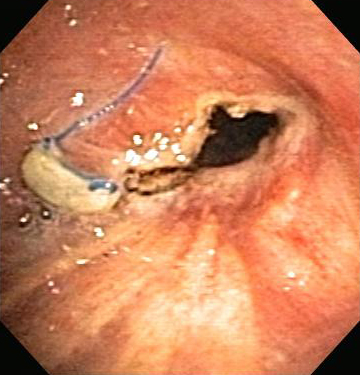

Стеноз дыхательных путей на фоне гранулематоза с полиангиитом (ранее именуемого гранулематозом Вегенера)

Из коллекций Хосе Фернандо Сантакруза, дипломированного врача, члена Американской коллегии специалистов в области торакальной медицины, DAABIP, и Эрика Фолка, дипломированного врача, магистра наук; используется с разрешения